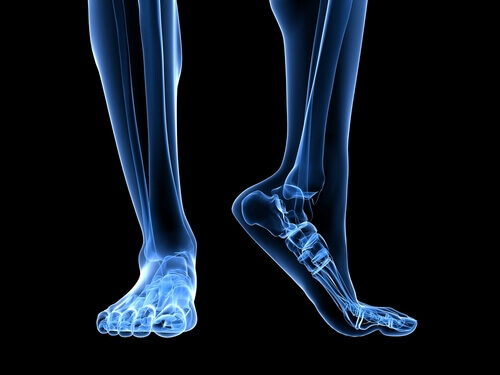

Ayağın anatomisi

Plantar bağın aşırı yüklenmesinde rol oynayan birkaç anatomik yapı vardır.

Aşil tendonu, genellikle calves kasları olarak bilinen gastroknemius kaslarını ve soleus kaslarını topuk kemiğine bağlayan bir bağdır. Aşil tendonunun geri çekilmesi plantar bağ üzerindeki baskıyı arttırır.

Anatomik yapıda akılda tutulması gereken bir başka faktör ayağın yere basışıdır. Düz taban veya yüksek pronasyona eğilimli ayaklar plantar bağı daha çok uzatır ve dokudaki fazla basınç nedeniyle yırtılma riski artar.